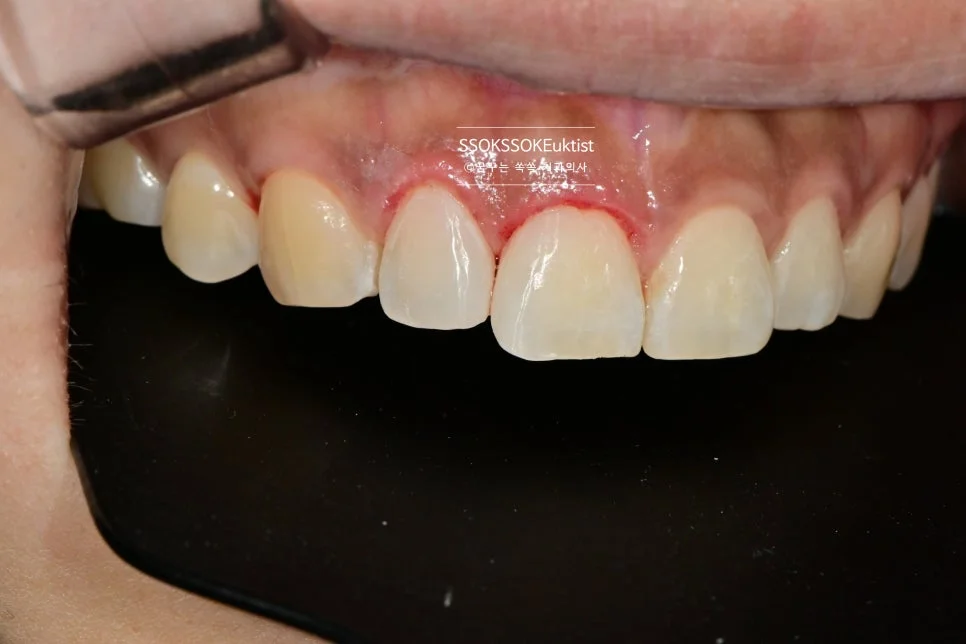

측면에서 바라본 사진입니다. 생각보다 틈이 커서 한 치아만 치료할 경우 한 개 치아만 너무 커 보이는 게 될 것 같아, 양쪽 치아 모두 레진으로 치료하는 것이 좋습니다.

그리고 안쪽에 닿는 점을 조정하여 치아가 벌어지는 경향을 최소화해주면 치료는 종결됩니다.

한 달 정도 후의 모습으로, 비교적 잘 유지되고 있는 것을 확인할 수 있습니다!